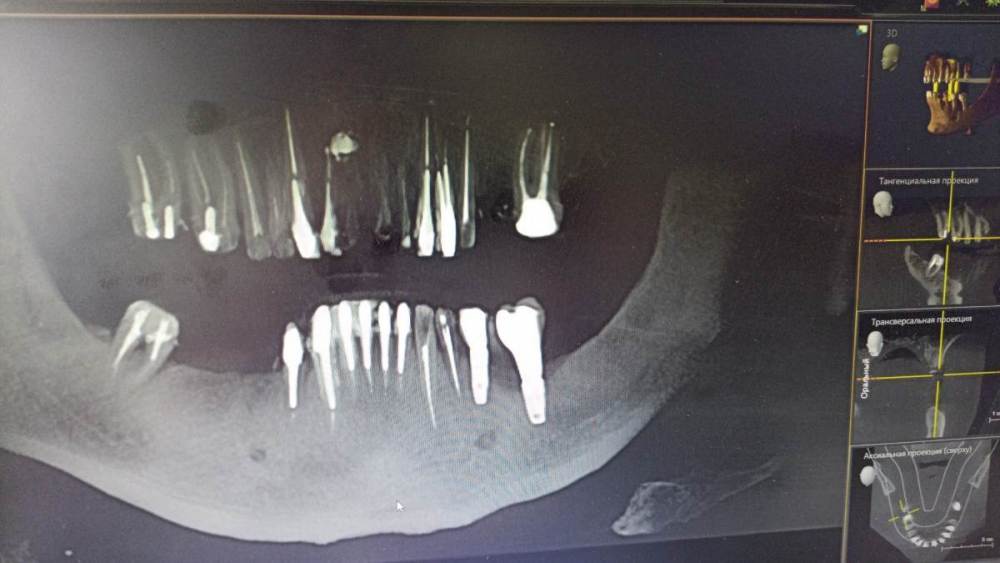

kramer Опубликовано 1 февраля, 2024 Поделиться Опубликовано 1 февраля, 2024 Здравствуйте, требуется компьютерная томография, чтоб ответить на ваш вопрос. Отправляйте, будем думать Ссылка на комментарий

Зндрю Опубликовано 2 февраля, 2024 Автор Поделиться Опубликовано 2 февраля, 2024 (изменено) КТ имеется . Окончание импланта лежит на нижней ветви тройничного нерва, но не травмирует его. Со слов независимого имплантолога, у которого был на консультации, иначе симптомы были бы неврологические , а их нет . Изменено 2 февраля, 2024 пользователем Зндрю Ссылка на комментарий

Зндрю Опубликовано 7 февраля, 2024 Автор Поделиться Опубликовано 7 февраля, 2024 (изменено) 01.02.2024 в 13:07, kramer сказал: Здравствуйте, требуется компьютерная томография, чтоб ответить на ваш вопрос. Отправляйте, будем думать Изменено 7 февраля, 2024 пользователем Зндрю Ссылка на комментарий

kramer Опубликовано 7 февраля, 2024 Поделиться Опубликовано 7 февраля, 2024 В принципе понятно. Лично мое мнение, что надо удалять оба имплантата (ближний выглядит недозаглубоенным (плохо видно), дальний слишком близко к нерву, что скорее всего и дает симптомы. Установить новые импланты, сделать мостовидную конструкцию. Ссылка на комментарий